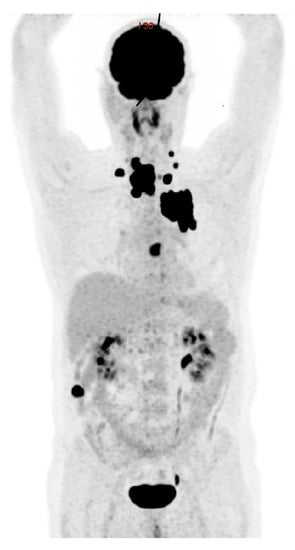

3.4.1. Radiodine Whole Body Scintigraphy

3.4.2. Positron Emission Tomography